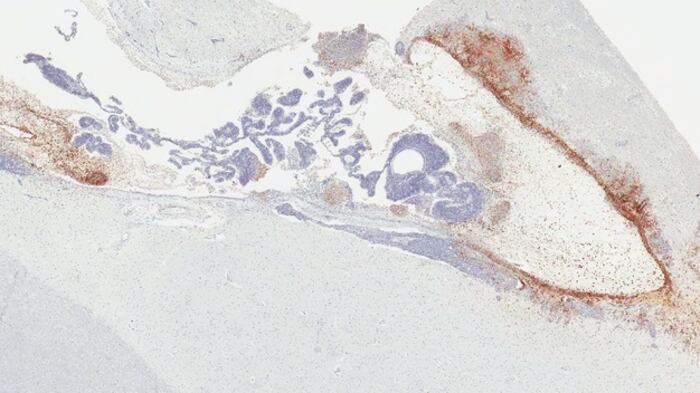

«El nuestro es el primer estudio que revela el escondite de la persistencia del virus del ébola en el cerebro y la patología que causa la posterior enfermedad mortal relacionada con el virus del ébola en el modelo de primate no humano. Descubrimos que alrededor del 20 por ciento de los monos que sobrevivieron al ébola tras el tratamiento con anticuerpos monoclonales seguían teniendo infección persistente, específicamente en el sistema ventricular del cerebro, en el que se produce, circula y contiene el líquido cefalorraquídeo, incluso cuando el virus del ébola se había eliminado de todos los demás órganos», explica el líder de la investigación, Kevin Zeng.

En particular, dos monos que inicialmente se recuperaron del ébola tras el tratamiento con anticuerpos monoclonales presentaron una recurrencia de los signos clínicos graves de la infección y sucumbieron a la enfermedad. La inflamación severa y la infección masiva por el virus del ébola estaban presentes en el sistema ventricular del cerebro; no se encontró ninguna patología evidente ni infección viral en otros órganos.

Durante los últimos años, el equipo de Zeng ha realizado estudios sistemáticos sobre la persistencia del virus utilizando como modelo a primates no humanos supervivientes. Esa investigación demostró que el virus, a pesar de haber sido eliminado de todos los demás órganos, puede esconderse y persistir en regiones específicas de órganos inmunes privilegiados, como la cámara vítrea de los ojos, los túbulos seminíferos de los testículos y el sistema ventricular del cerebro, según se informa en este estudio.